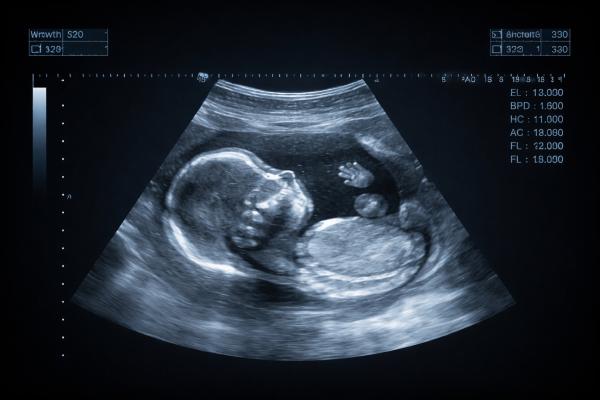

Anomaly Scan (Level II Scan)

A detailed scan to examine the baby’s organs, spine, brain, heart, and limbs.